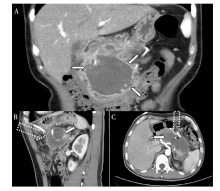

许克东, 马振华, 曹芳, 仵正. 重症急性胰腺炎腹腔不同分区局部并发症的微创治疗[J]. 外科理论与实践, 2022, 27(01): 46-51.

XU Kedong, MA Zhenhua, CAO Fang, WU Zheng. Minimally invasive treatment for local complications of patients with severe acute pancreatitis in different abdominal partitions[J]. Journal of Surgery Concepts & Practice, 2022, 27(01): 46-51.